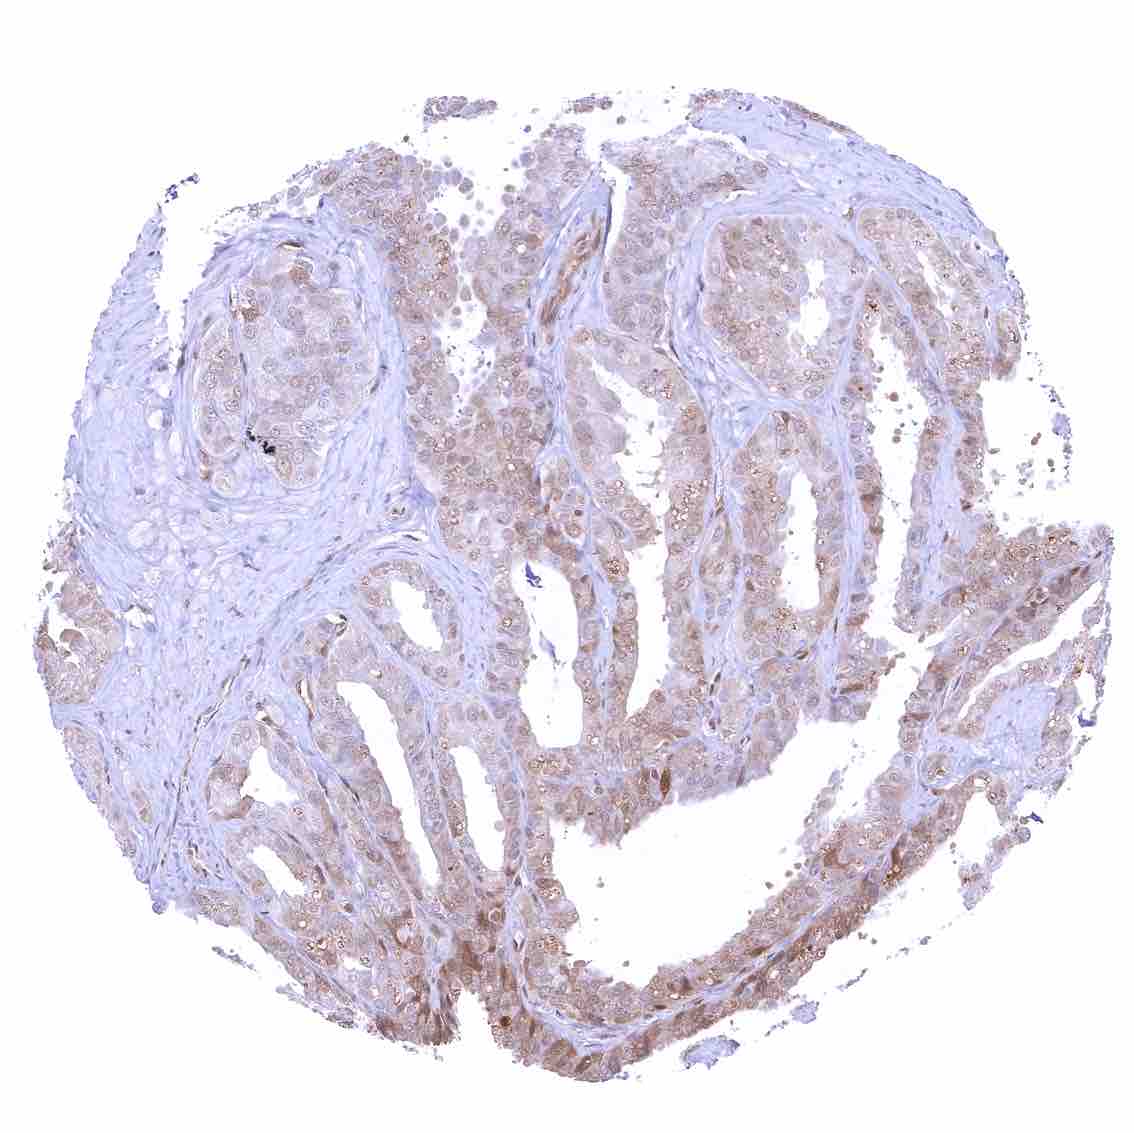

Prostate